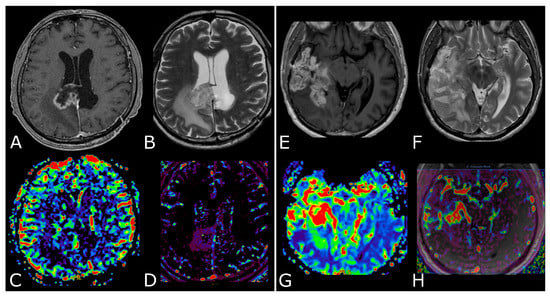

3. MR Perfusion

3.2. Clinical Applications

3.2.1. Differentiating HGG from LGG and Clinical Prognosis

3.2.2. Differentiating Tumors on the Basis of the Genetic Profiles

3.2.3. Differentiating Recurrent Tumor from Pseudoprogression and Radiation Necrosis and Be Aware of Pseudoresponse

4. Diffusion Weighted and Diffusion Tensor Imaging